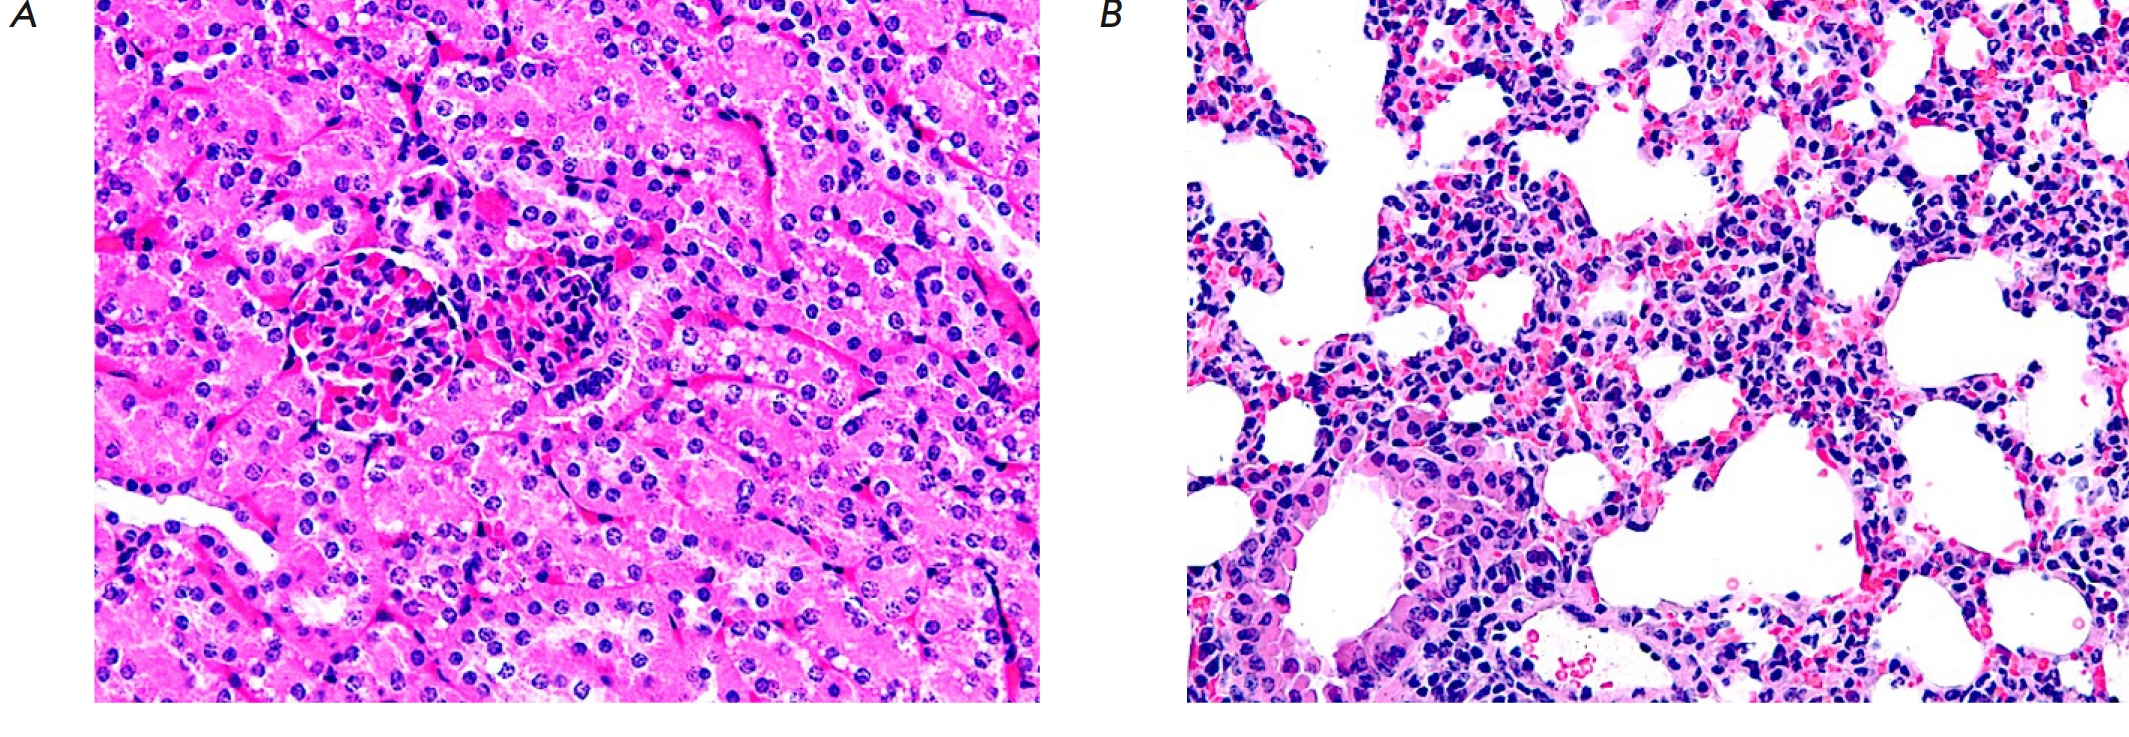

Рис. 3. Фрагмент ткани печени подопытной мыши после введения 5'- нораристеромицина в дозе 80 мг/кг. Гепатоциты с фрагментированным ядром – апоптотические клетки (показаны стрелкой), округлые клетки с гомогенной цитоплазмой – некротические клетки. Окраска гематоксилином-эозином. Увеличение 100 (А); 400 (Б)

В ткани печени отмечали тотальную дискомлексацию печеночных балок, выраженный перипортальный стеатоз в сочетании с центролобулярными участками гибели гепатоцитов (рис. 3А). При этом, согласно морфологическому исследованию, в гибели части печеночных клеток были признаки апоптоза, а другая часть клеток подвергалась некротическим изменениям (рис. 3Б). В относительно сохранных гепатоцитах отмечали или пикноз ядер, или перераспределение хроматина в подмембранное пространство ядра.

В почках подопытной мыши отмечали стазирование и сладжирование эритроцитов в капиллярной системе клубочков и межтубулярного пространства. Просвет многочисленных извитых канальцев был сужен вследствие гипертрофии выстилающих их эпителиоцитов, а в цитоплазме клеток присутствовали многочисленные вакуоли (рис. 5А). В легочной ткани подопытной мыши отмечалась инфильтрация полиморфноядерными нейтрофилами межуточной ткани легкого. Также регистрировали утолщение и отек альвеолярных перегородок, явления диапедеза эритроцитов в межальвеолярные перегородки (рис. 5Б).

Рис. 5. Фрагмент ткани почки (А) и легкого (Б) подопытной мыши после введения 5'- нораристеромицина в дозе 80 мг/кг. Окраска гематоксилином-эозином. Увеличение 400